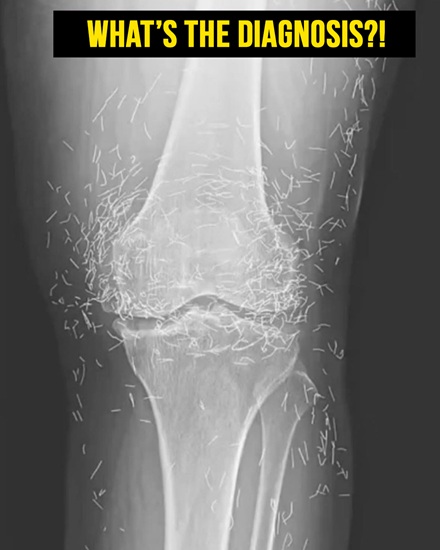

Doctors Discover Unexpected Treasure in Woman’s Knees

When a 65-year-old woman from South Korea went to a clinic for persistent knee pain, doctors expected a standard case of osteoarthritis. What they found, however, surprised everyone and would make headlines in medical journals.